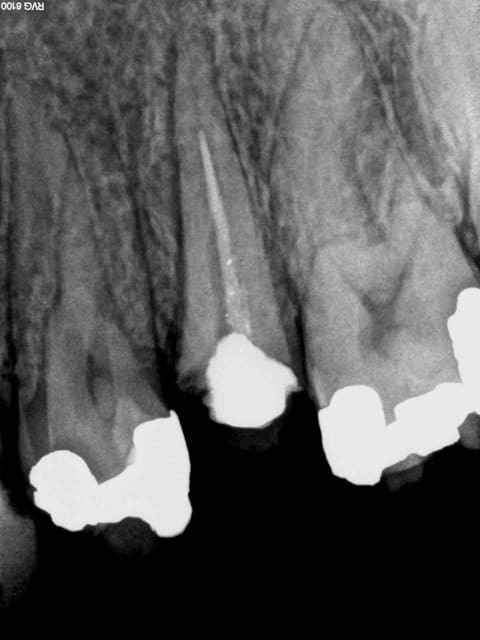

Souvent il n'y a rien, c'est plus facile. On peut d'ailleurs illustrer en quasi direct ses propos tellement c'est fréquent. Cas tous frais.-)))))

1 bd9s5w - Eugenol

2 c9r7kc - Eugenol

3 wheqza - Eugenol

4 ass1cx - Eugenol